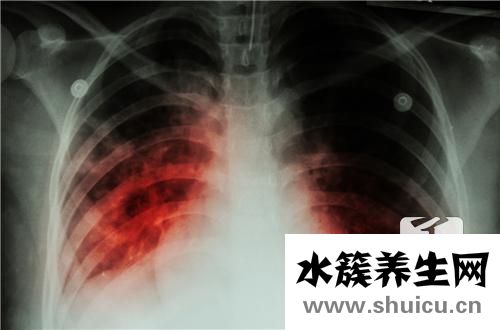

?眾所周知,結核分枝桿菌是一種具有較高感染率的病毒。 例如,結核病是生活中的常見疾病,是由結核分枝桿菌引起的疾病。 在協助存在結核感染的患者的過程中,結核皮膚檢查已成為非常重要的輔助方法,那么結核皮膚檢查如何看待結果呢?

結核菌素試驗也叫“OT”試驗,是判斷有無結核病的一種早期輔助診斷方法。當結核菌進入人體后,經四至八周機體產生對結核菌的過敏反應。此時做結核菌素試驗就出現陽性反應。目前國內通用皮內注射法,具體作法是:用1:2000稀釋液0.1毫升(5單位)注入前臂掌側中、下1/3交界處皮內,使之為直徑6~10毫米的皮丘。

注射后48與72小時觀察結果,以局部紅暈硬結的直徑大小來判斷其反應的強度。

用卡尺測量硬結縱橫直徑,硬結平均直徑=(縱徑+橫徑)/2。

硬結平均直徑如小于5mm為陰性,大于等于5mm小于20mm為陽性反應[5~9mm為弱陽性(+),10~19mm為陽性(++)],20mm以上(+++)或局部有水皰、壞死、淋巴管炎均為強陽性。

利用結核菌素在人體皮膚上進行試驗,可以判斷受試者是否感染過結核桿菌。試驗結果報告的意義主要為:

1、結核菌素試驗陽性,表示受試者曾經受到過結核菌感染或已經接種過卡介苗,但不能判定其是否患有結核病。

2、結核菌素試驗強陽性,表示體內有活動性結核菌。

3、對于3歲以下,特別是1歲以下尚未接種過卡介苗的小兒,如果結核菌素試驗陽性反應,則表示體內有新的結核病灶。年齡越小,患活動性結核的可能性越大。

4、如果兩年之內結核菌素皮試結果由陰性轉為陽性,或反應強度從原來的硬結直徑小于10毫米增至大于10毫米,提示新近感染過結核菌,或可能存在活動性病灶。

5、結核菌素試驗陰性,表示受試者未受到過結核菌感染,也未接種過卡介苗,或接種未成功。

6、應該注意的是,某些情況下同樣會引起結核菌素試驗呈現陰性反應;如當機體免疫功能低下或受抑制時,(如嚴重營養不良、重癥結核等),可呈假陰性反應。